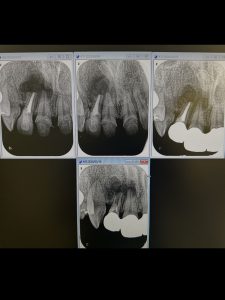

Internal apicoectomy

昨年根切した部位が再燃?

一度は病巣縮小したが、久しぶりに来院したら

舌側骨板が破壊され、排膿している

根裏側舌側の感染源不完全除去か、更には2番ガイドによる力の影響か?

根管経由で意図的に根尖部破壊し、舌側に薬剤、レーザーが届き易く切断

根管経由と舌側排膿路2箇所から各2分づつ照射にカルビタールと!

週1回を4週連続、その後は3〰︎4週に1回洗浄レーザー